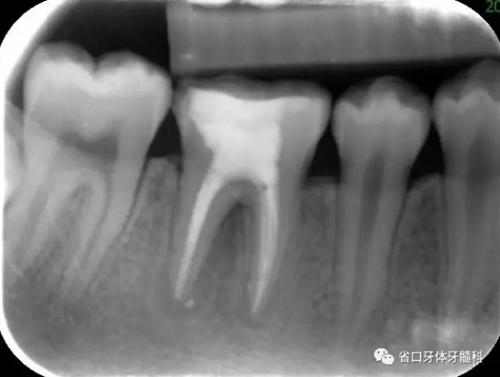

圖3 根管治療術(shù)后4個(gè)月